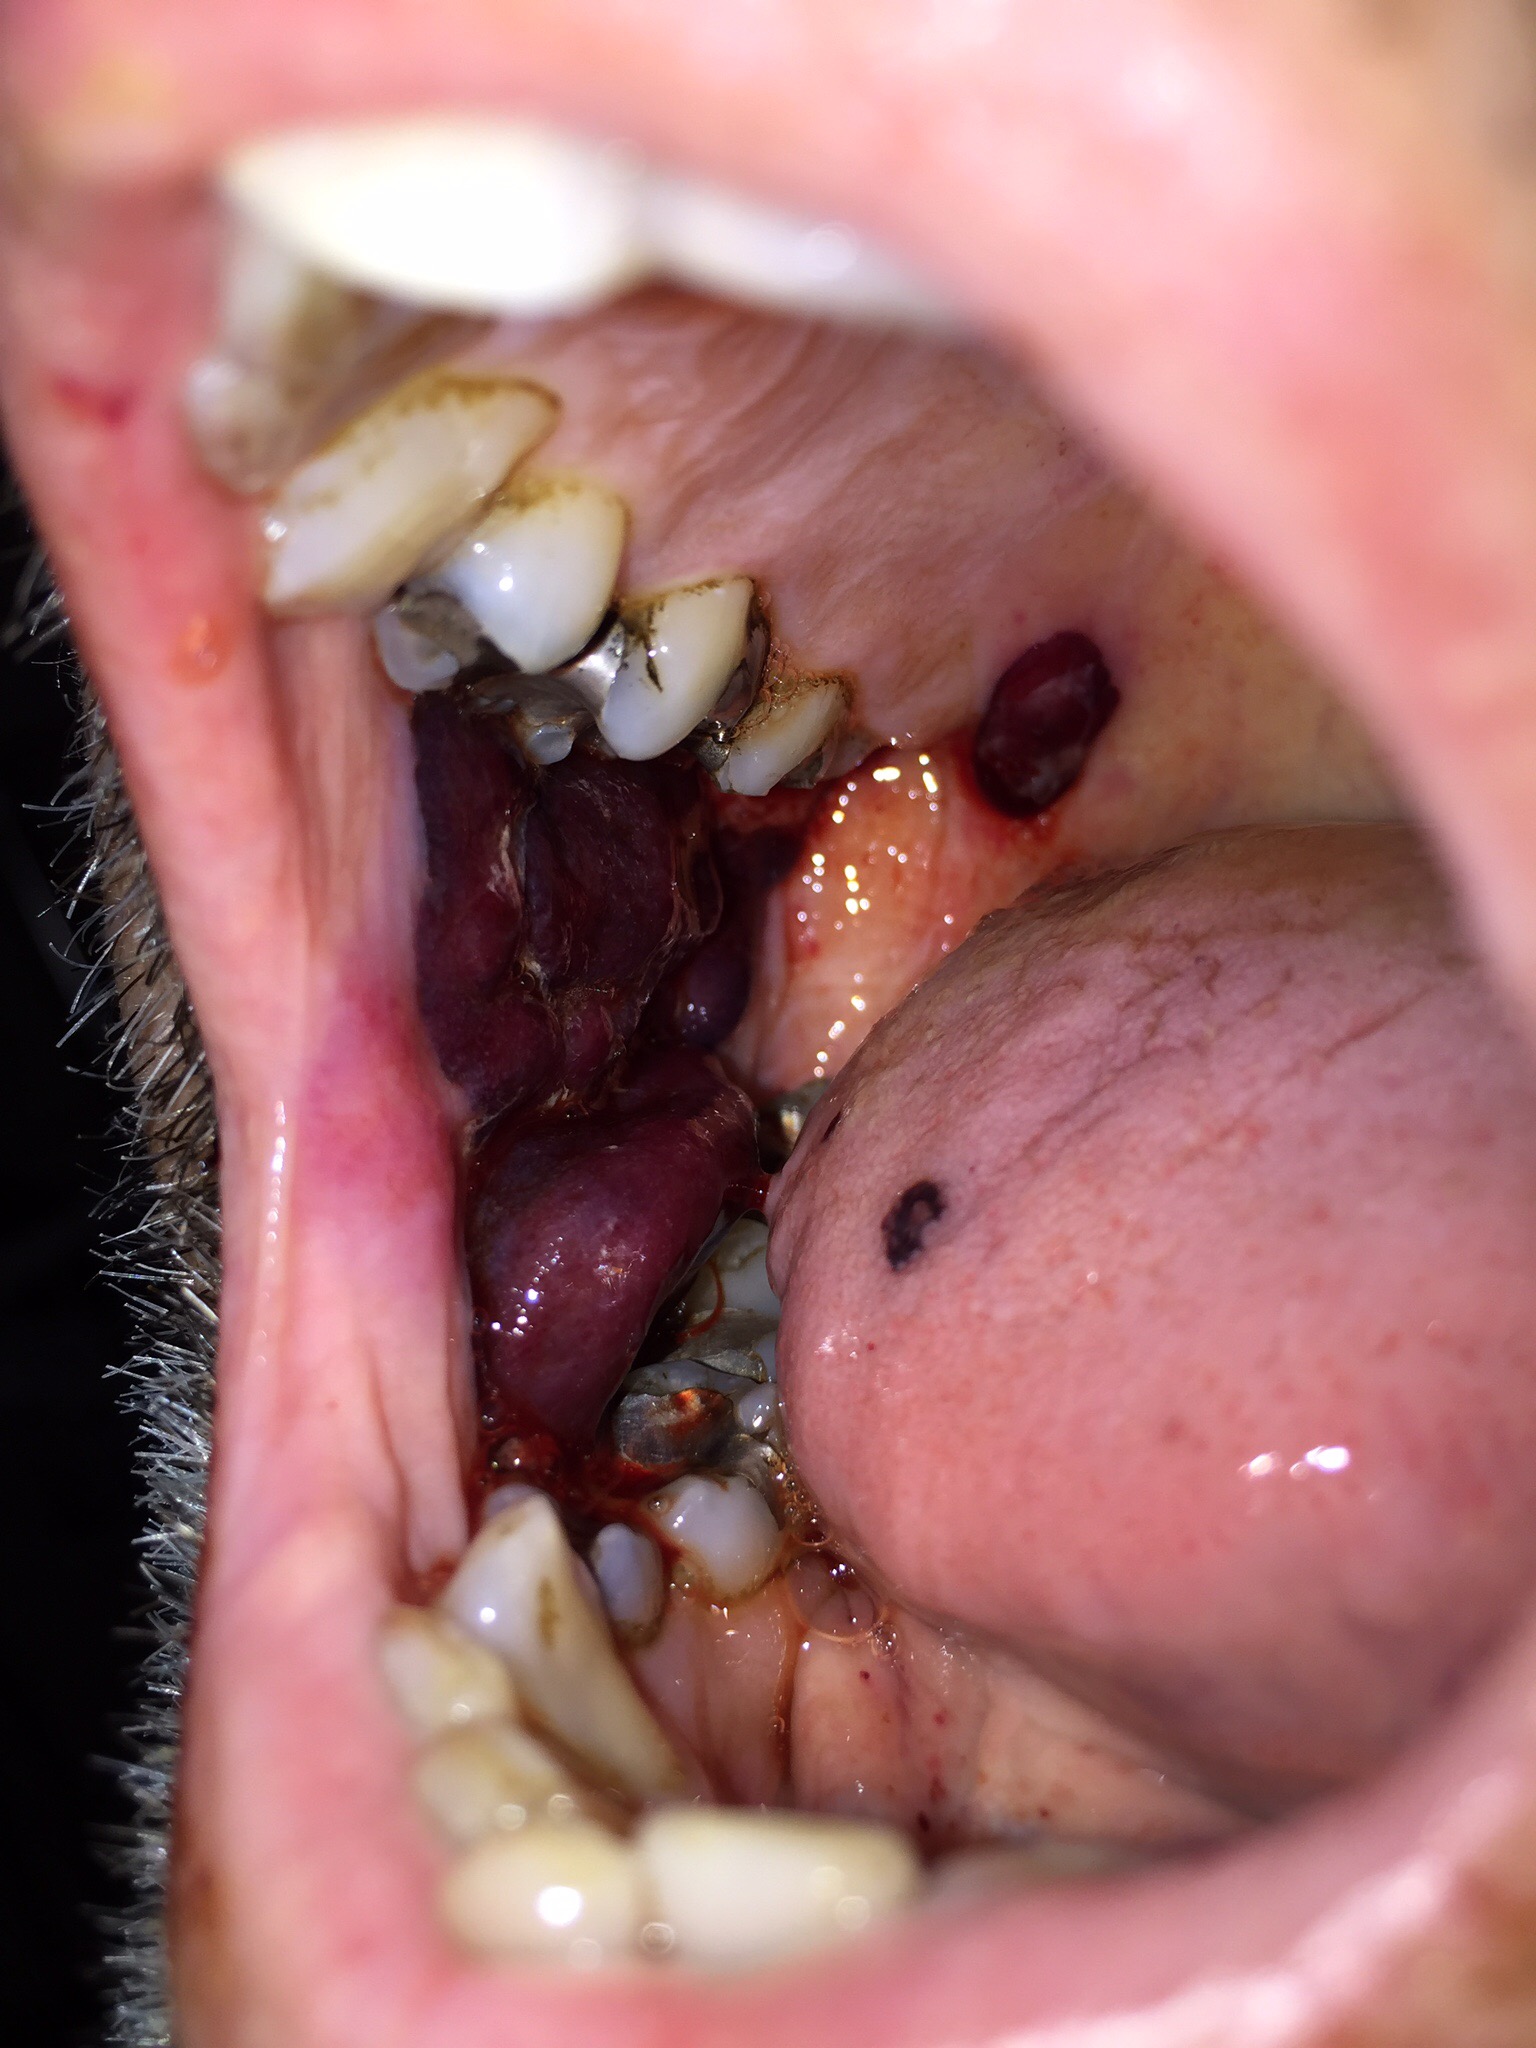

Got up early and headed south what a wet journey, loads of puddles on the road. I got back to the Beatson about 10am and after I calmed down we didn’t have to bad a day.they have taken him of the pain drip that was in his arm and are giving him tablets that are not morphine based. Seems to be working ok together with hot pads and massage.he has a horrible big blood blister in his mouth, they are giving him platelets which should help that and he has also had two units of blood. His temperature has been down so all good really. Not eaten as much as he could have but has had cocoa pops and a yoghurt. A woman came over from friends of the Beatson and gave Roger a massage on his lower legs and feet which he enjoyed and found relaxing. A much better day all round really.

Roger had a good night which was great but he a had a bad reaction to something and ended up on oxygen and was very weak. Went on all morning, we got him washed and I helped him do his mouth. His pulse is back ok, he has a has a small infection from his line but they are giving him antibiotics. His temperature has been ok and his pulse and blood pressure are back ok. We did his mouth twice today.